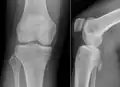

Die Begriffe Osteochondrom, Ekchondrom und kartilaginäre Exostose beschreiben gutartige Knochentumoren. Solange der Tumor nicht verknöchert ist, spricht man vom Ekchondrom oder kartilaginärer Exostose. Als Osteochondrom wird der Tumor nach Verknöcherung bezeichnet. Diese Tumoren wachsen gestielt vom gelenknahen Knochen (Metaphyse) aus. Es sind die häufigsten gutartigen Knochentumoren. Sie machen sich meistens durch Wachstum im Kindesalter bemerkbar. Nach Abschluss des Knochenwachstums im Erwachsenenalter wachsen die Tumoren meist nicht weiter.